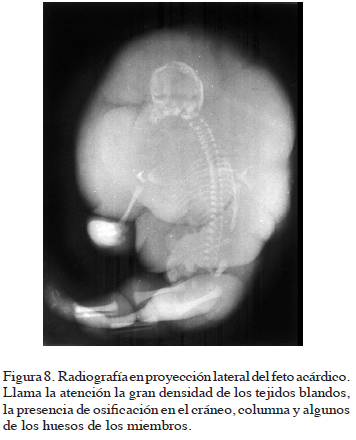

ESTUDIO RADIOLÓGICO

En las placas radiográficas llama la atención la gran densidad de los tejidos blandos, sobre todo en la región de la cabeza y el tronco.

La radiografía lateral permite la visualización de un cráneo muy pequeño. La base del cráneo presenta gran alteración en su desarrollo, razón por la cual no pueden diferenciarse sus componentes. El viscerocráneo tiene una osificación deficiente (Figura 8).

La columna vertebral se observa en toda su extensión, el segmento cervical es largo y consta de ocho vértebras. Los arcos costales se presentan en forma rectilínea y sólo se observan once pares. Las vértebras lumbares y sacras tienen una osificación aparentemente normal.

En la cintura escapular se observa osificación deficiente de la clavícula y de la escápula. Los huesos del brazo y antebrazo tienen osificación aparentemente normal. En cada mano se observan tres metacarpianos y en la mano izquierda se observan dos falanges.

En la cintura pélvica hay osificación de los huesos ilíacos, con sus escotaduras ciáticas dirigidas hacia la línea media. De igual modo se observan los puntos de osificación del isquion, pero no hay osificación del pubis. Los miembros inferiores presentan todos sus segmentos óseos, a excepción de los del pie. El pie izquierdo no tiene ninguna osificación, mientras que el pie derecho muestra un punto para el calcáneo, dos metatarsianos y dos pequeños puntos para dos falanges.

La presencia de un punto de osificación en el calcáneo, nos indica una edad aproximada de siete meses.